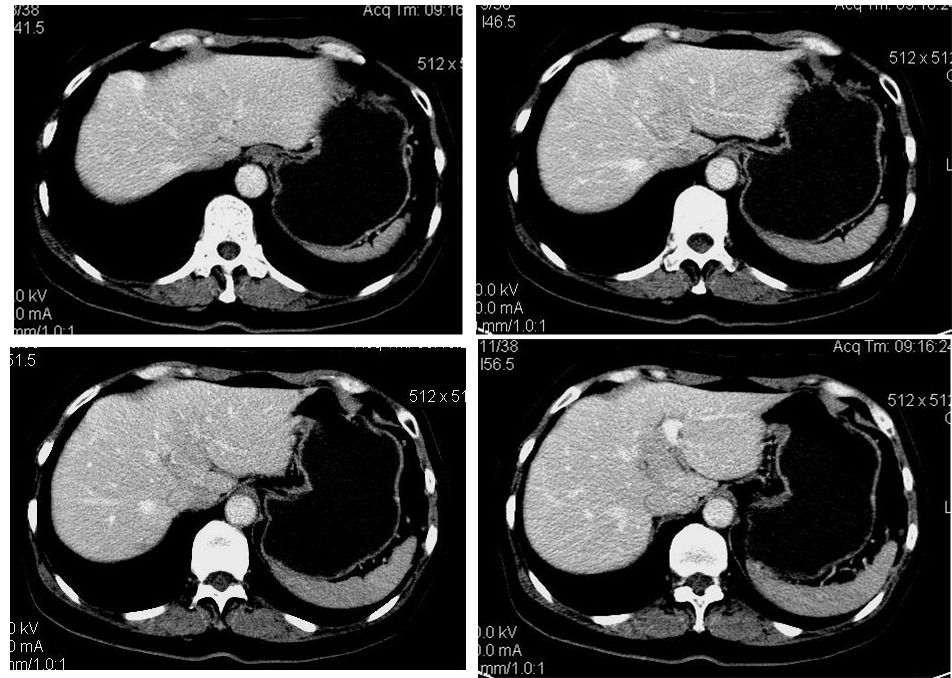

患者,女,65岁,住院准备甲状腺腺瘤用术,术前常规发现肝脏占位,ct增强扫描。

平扫

动脉期

门脉期

延迟扫描

肝左叶内侧段低密度灶,增强明显快进快出表现,考虑:肝癌。

学习了,这可能是脂肪含量少的血管平滑肌脂肪瘤,因血管丰富所以动脉期密度升高明显,但该患无肝硬化表现,所以,诊断肝癌,依据不足.谢谢上传.对今后工作是一个提醒.